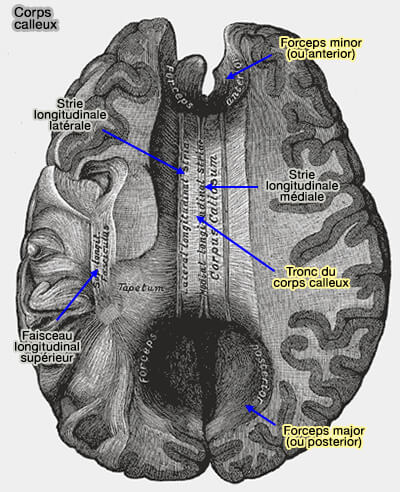

Corps calleux (vue ventrale)

(Figure : vetopsy.fr)

Fibres du corps calleux

1. Les radiations du corps calleux sont des fibres du corps calleux qui irradient dans la substance blanche des deux hémisphères.

a. Les deux forceps sont des fibres en U qui unissent :

• les deux lobes frontaux au niveau du genou pour former le forceps minor (ou anterior) ;

• les deux lobes occipitaux dans le bourrelet pour former le forceps major (ou posterior).

b. Le tapetum, entre les deux forceps, est formé de du groupe principal de fibres qui s'étendent latéralement de chaque côté dans le lobe temporal et recouvrent la partie centrale du ventricule latéral.

Le tapetum et la commissure antérieure relient les lobes temporaux gauche et droit.